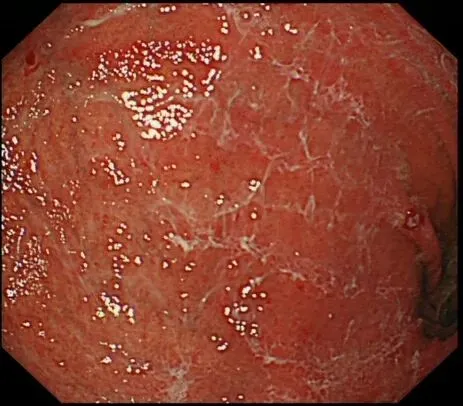

蛛网状黏液(web-like mucus):以胃底、胃体大弯为中心,有时可见白色透明、水洗难以去除的黏液附着,因外观与蜘蛛网相似而命名,多见于口服钾离子竞争性酸阻滞剂(P-CAB)患者,可能是因为其强效、持续抑酸作用所致,具体机制尚需进一步研究明确。

(报道称黏膜斑状或线状发红也是P-CAB药物所致,原因不明

个人体会:蛛网状黏液与P-CAB药物相关,顽固性黏液与AIG相关,两种胃内环境都一样是胃酸缺乏,据说胃内PH升高可导致蛋白质变性形成“乳状”黏附,也据说是因为胃酸缺乏导致化生的黏液分泌细胞大量增多,分泌异常成分的高粘稠度黏液,两者的形成机制和内镜表现是比较类似的,不同之处在于蛛网状黏液除了比较“网状”之外,还比较“拉丝”、“乳白”,顽固性黏液比较“果冻”、“淡白”、"广泛涂层"、“紧贴大地”。。。词穷了,从小没学过语文课,还需多看书、观察更多病例加以总结,请各位老师们指正。。。